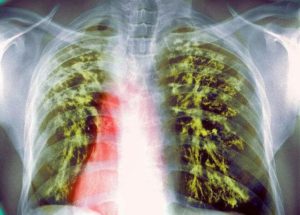

Рентген признаки при туберкулезе и пневмонии

Основной метод выявления туберкулеза – это флюорография. Но в некоторых случаях проводится и рентген легких. При пневмонии врачи предпочитают рентгеноскопию.

На снимке можно четко определить, в какой степени поражены легкие при туберкулезе и пневмонии, где локализуются очаги.

Признаки на рентгене:

- При воспалении легких чаще поражается нижняя часть обоих легких. Тени, показывающие наличие очага при туберкулезе, расположены, как правило, в одном легком в верхнем или среднем сегменте.

- Очертания очагов поражений. Для пневмонии характерны размытые тени, пораженные легкие словно задымлены на определенных участках. При туберкулезе границы очагов очерчены, они имеют четкий контур на рентгеновских снимках.